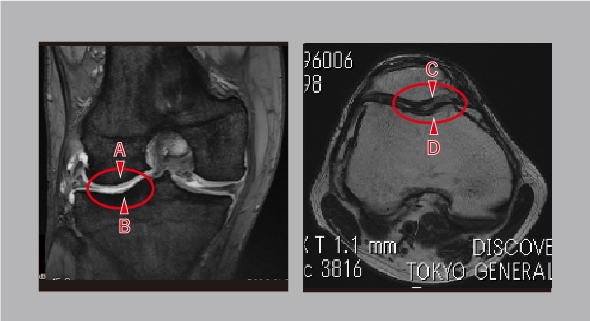

大腿骨と脛骨があたる部分(外側)と膝蓋骨と大腿骨があたる部分の合計4カ所に軟骨欠損がありました。

自家培養軟骨移植術は、A、C、Dの場所におこないました。Bも治療したかったのですが、手術時にアプローチがしづらく、これ以上、傷口を広げて無理に処置することは、後に椎名選手の膝の機能に悪影響を与えると判断しました。

1年2ヵ月後のMRI画像を術前画像と比較すると、培養軟骨を移植した後、不整な白い部分がなくなり、周りの健常な軟骨と馴染んできているのがわかります。